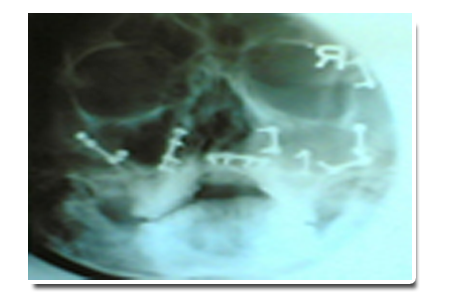

X-ray view of plating surgery done in fracture lower jaws as shown below:

X-ray view of plating surgery done in all facial bones as shown below: